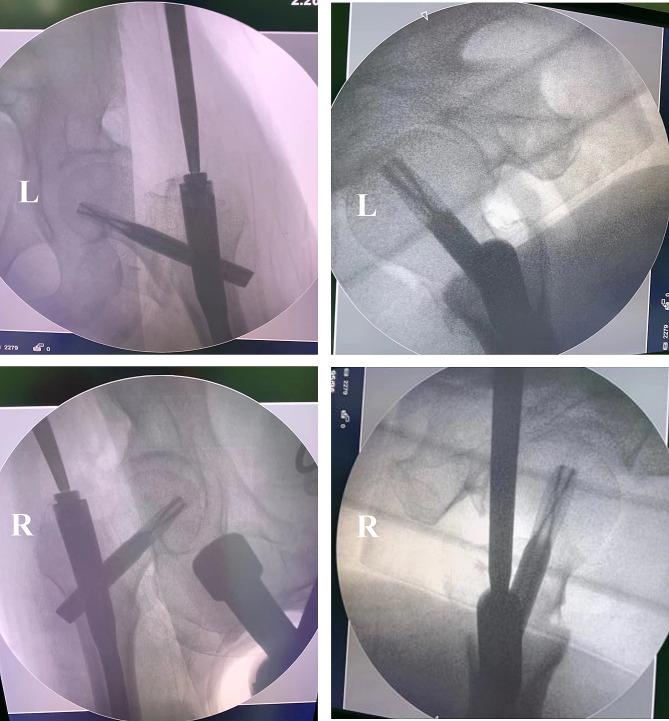

We report on an 84-year-old male who suffered severe trauma from a car accident, resulting in multiple injuries and shock state, with pain and limited mobility in both hip joints. After examination and imaging studies, the patient was diagnosed with multiple injuries and bilateral intertrochanteric fractures. Following emergency resuscitation, he was admitted to the orthopedic ward. A pre-surgical multidisciplinary team (MDT) consultation was convened to optimize surgical conditions. The patient underwent successful one-stage bilateral intramedullary nailing. The patient was assisted to stand with a walker on the third day after surgery. Six months post-surgery, the patient resumed outdoor activities.

我们报告了一例 84 岁男性患者,因车祸遭受严重创伤,导致多发伤和休克状态,双侧髋关节疼痛且活动受限。经检查和影像学研究,患者被诊断为多发伤和双侧转子间骨折。在紧急复苏后,他被收入骨科病房。为了优化手术条件,进行了术前多学科团队(MDT)会诊。患者成功接受了一期双侧髓内钉固定术。术后第 3 天,患者在助行器的辅助下站立。术后 6 个月,患者恢复户外活动。